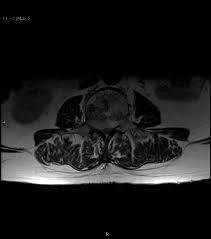

5.2 computed tomography (ct) scans. Symptoms of chordomas can include back pain, numbness, headaches, and vision problems. The life expectancy for people with a chordoma depends on their age, the type of the tumor, the size and location of the tumor, and other factors. They often recur after treatment, and in about 40 percent of cases the cancer spreads ( metastasizes) to other areas of the body. Chordomas are generally slow growing and are most commonly found within the head at the base of the skull near a bone called the clivus and in the lower portion of the spine.